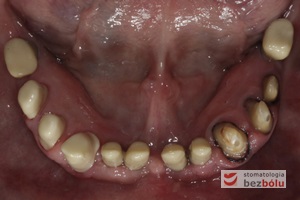

Stan wyjściowy - patologiczne wychylenie zębów górnych, liczne braki zębowe w szczęce i żuchwie, nieproporcjonalnie małe zęby do podstaw kostnych

Stan wyjściowy – patologiczne wychylenie zębów górnych, liczne braki zębowe w szczęce i żuchwie, nieproporcjonalnie małe zęby do podstaw kostnych

Braki zębowe w strefach bocznych szczęki i żuchwy - widoczne starcie patologiczne na skutek przeciążeń okluzyjnych w odcinku przednim

Braki zębowe w strefach bocznych szczęki i żuchwy – widoczne starcie patologiczne na skutek przeciążeń okluzyjnych w odcinku przednim